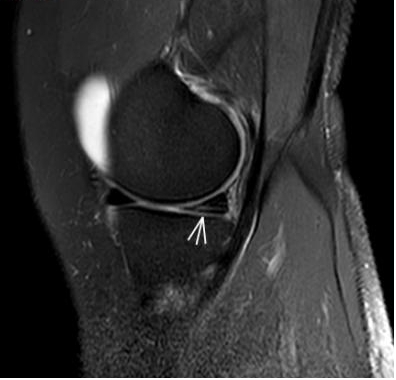

3. 上下樓“針刺痛”——軟骨的“磨砂紙預(yù)警”

場(chǎng)景:爬樓梯時(shí)膝蓋刺痛,久坐后僵硬如“生銹齒輪”

MRI偵查:發(fā)現(xiàn)軟骨變薄、缺損(早期骨關(guān)節(jié)炎信號(hào)),趕在“路面塌方”前修復(fù)

(軟骨損傷)